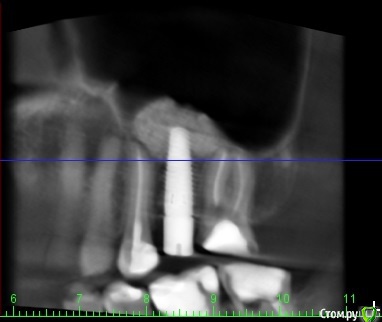

венди Опубликовано 26 января, 2017 Поделиться Опубликовано 26 января, 2017 (изменено) Добрый день! Не знаю в какой раздел будет правильно добавить, т.к. проблема смешанная. Помогите, пожалуйста! 3 месяца мучений. В прошлом году начала заниматься зубами. Был сделан панорамный снимок (прилагаю).В мае в районе отсутствующего 26 был установлен имплант с одновременным открытым синус-лифтингом. Послеоперационный период протекал более-менее нормально. Меня отпустили на пол года. И я стала заниматься остальными зубами. Лечили кариес справа, был удален 46 (резорбация мед. стенки медиального корня с перфорацией). К осени добрались до левой нижней стороны. 26.09. - был залечен кариес в 36 зубе. После этого зуб стал стрелять током при накусывании. Врач решила ещё понаблюдать.19.10. - 37 зуб с гранулемой был распломбирован, врач прошла каналы, заложила кальций. Через 6 дней ещё раз все прочистили, запломбировали каналы полностью, поставили временную пломбу и сказали, что можно протезироваться. Вроде зуб после лечения не беспокоил.01.11. - я пошла на осмотр к хирургу по поводу удаленного 46. Хирург решил раскрыть имплант, т.к. уже время подошло. Сказал всё хорошо прижилось и поставил формирователь десны. С этого дня моя жизнь разделилась на до и после.. Стала болеть вся область вокруг импланта, появилось ощущение мешающего валика под щекой, формирователь утонул в десне, отечность в этой области была. Обобщу и скажу, что после этого формирователь перекручивался еще 3 раза, внутри все промывалось, я принимала антибиотики. Острые ощущения немного ушли, но дискомфорт мешающий нормально жить оставался. По снимку - все отлично, имплант интегрирован (прилагаю). Одновременно с этими манипуляциями с имплантом 36 зуб стал не только бить током, а до него уже нельзя было дотронуться. 18.11 - вскрыли, депульпировали, заложили кальций и через неделю закрыли все постоянной пломбой (снимок прилагаю). Всё это время, впрочем как и сейчас вся левая сторона была охвачена ужасными ощущениями. Распирание, нытье, давящая боль, дискомфорт и днем и ночью. Стала плохо спать. Перед Новым Годом хирург принял решение выкрутить формирователь и посмотреть за динамикой. Мне показалось, что стало немного легче, особенно что касается ощущение валика под щекой. НО все равно с левой стороны мне что-то болит. От области импланта ли это идет или от 36-37 - я не знаю, не могу точно дифференцировать.... т.к. ковырялись везде одновременно и у меня уже все спутано... Никто не может понять, что со мной, т.к. по снимкам и 3Д все отлично. На прошлой неделе придя в очередной раз в клинику - по панорамному снимку и моим жалобам на боли поставили диагноз "дисфункция ВНЧ, артроз ВНЧС слева". При этом я спокойно открываю рот без болей, щелчков и хруста, при жевании тоже ничего не болит. Назначили физио и Аэртал - принимаю больше недели вообще все без изменений... аэртал даже не обезбаливает особо. На данный момент я ощущаю постоянный тупой ноющий тянущий дискомфорт слева. Чувство распирания. Поднимается иногда температура 37-37,1. Плохо сплю, нервничаю, т.к. очень снизилось качество жизни. Помогите, пожалуйста, разобраться. На что бить, если по снимками как бы все хорошо?! Имплант, 36, 37, сустав?? Все началось с раскрытия имланта. До этого я жила обычной жизнью. Есть 3Д декабрьские. Если кто-то захочет посмотреть я добавлю. Спасибо! Изменено 26 января, 2017 пользователем венди Ссылка на комментарий

inSight Опубликовано 12 февраля, 2017 Поделиться Опубликовано 12 февраля, 2017 смотреть за динамикой. Неужели эту боль придумывает голова? У меня уже сил нету это терпеть. До лечения ведь вообще ничего не болело. Тянет-распирает-ноет-давит преимущественно снизу в районе 36 и 37 зуба. Но как его раскрывать, когда откуда-то идёт давяще-ноющее-распирающее ощущение? я затрудняюсь ответить, не нравится мне ваш 27 зуб смотрю кт и вот не пойму толь пропущенная анатомия. Нужна помощь более опытных. Ссылка на комментарий